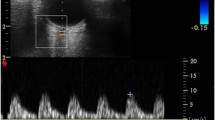

Imaging

LSCI imaging was performed on a weekly basis, concurrent with standard ROP screening eye examination. Both eyes were imaged during each LSCI session, with the goal of one high quality image per eye per session. LSCI sessions were deferred if a subject was medically unstable. Retinal blood flow imaging with LSCI was conducted using the investigational XyCAM NEO prototype system (Vasoptic Medical, Inc., Columbia, MD, USA). The XyCAM prototype is an adaptation of the FDA-cleared XyCAM RI System (Vasoptic Medical, Inc., Columbia, MD, USA) that is mounted with a movable arm. The XyCAM NEO also has software customized for imaging retinal blood flow in supine infants in the NICU. XyCAM uses LSCI to obtain retinal blood flow data within a 25-degree field of view. In this study, the field of view was approximately centered on the optic nerve head by adjusting the relative positioning of the XyCAM with respect to the neonate’s eye. High frame-rate image data was acquired for duration of six seconds from each eye under near-infrared laser illumination (peak wavelength of 785 nm), with BFV index computation at every pixel. Focusing under laser illumination was assisted via visualization of blood flow velocities computed in real-time and depicted in pseudo-color13. The data was accepted if it contained a contiguous stretch of at least 2 s of 3 or greater artifact-free blood flow pulses (cardiac cycles) without significant motion of the eye. If spontaneous motion occurred, the image capture attempt was repeated up to 2 times, for a total XyCAM exam duration of no more than 10 min. Immediately following LSCI data collection protocol, the standard ROP eye screening exam was conducted with binocular indirect ophthalmoscopy followed by retinal photography using the RetCam 3 Shuttle (Natus Medical Inc., Middleton, WI, USA) if clinically indicated for advanced or progressive ROP.